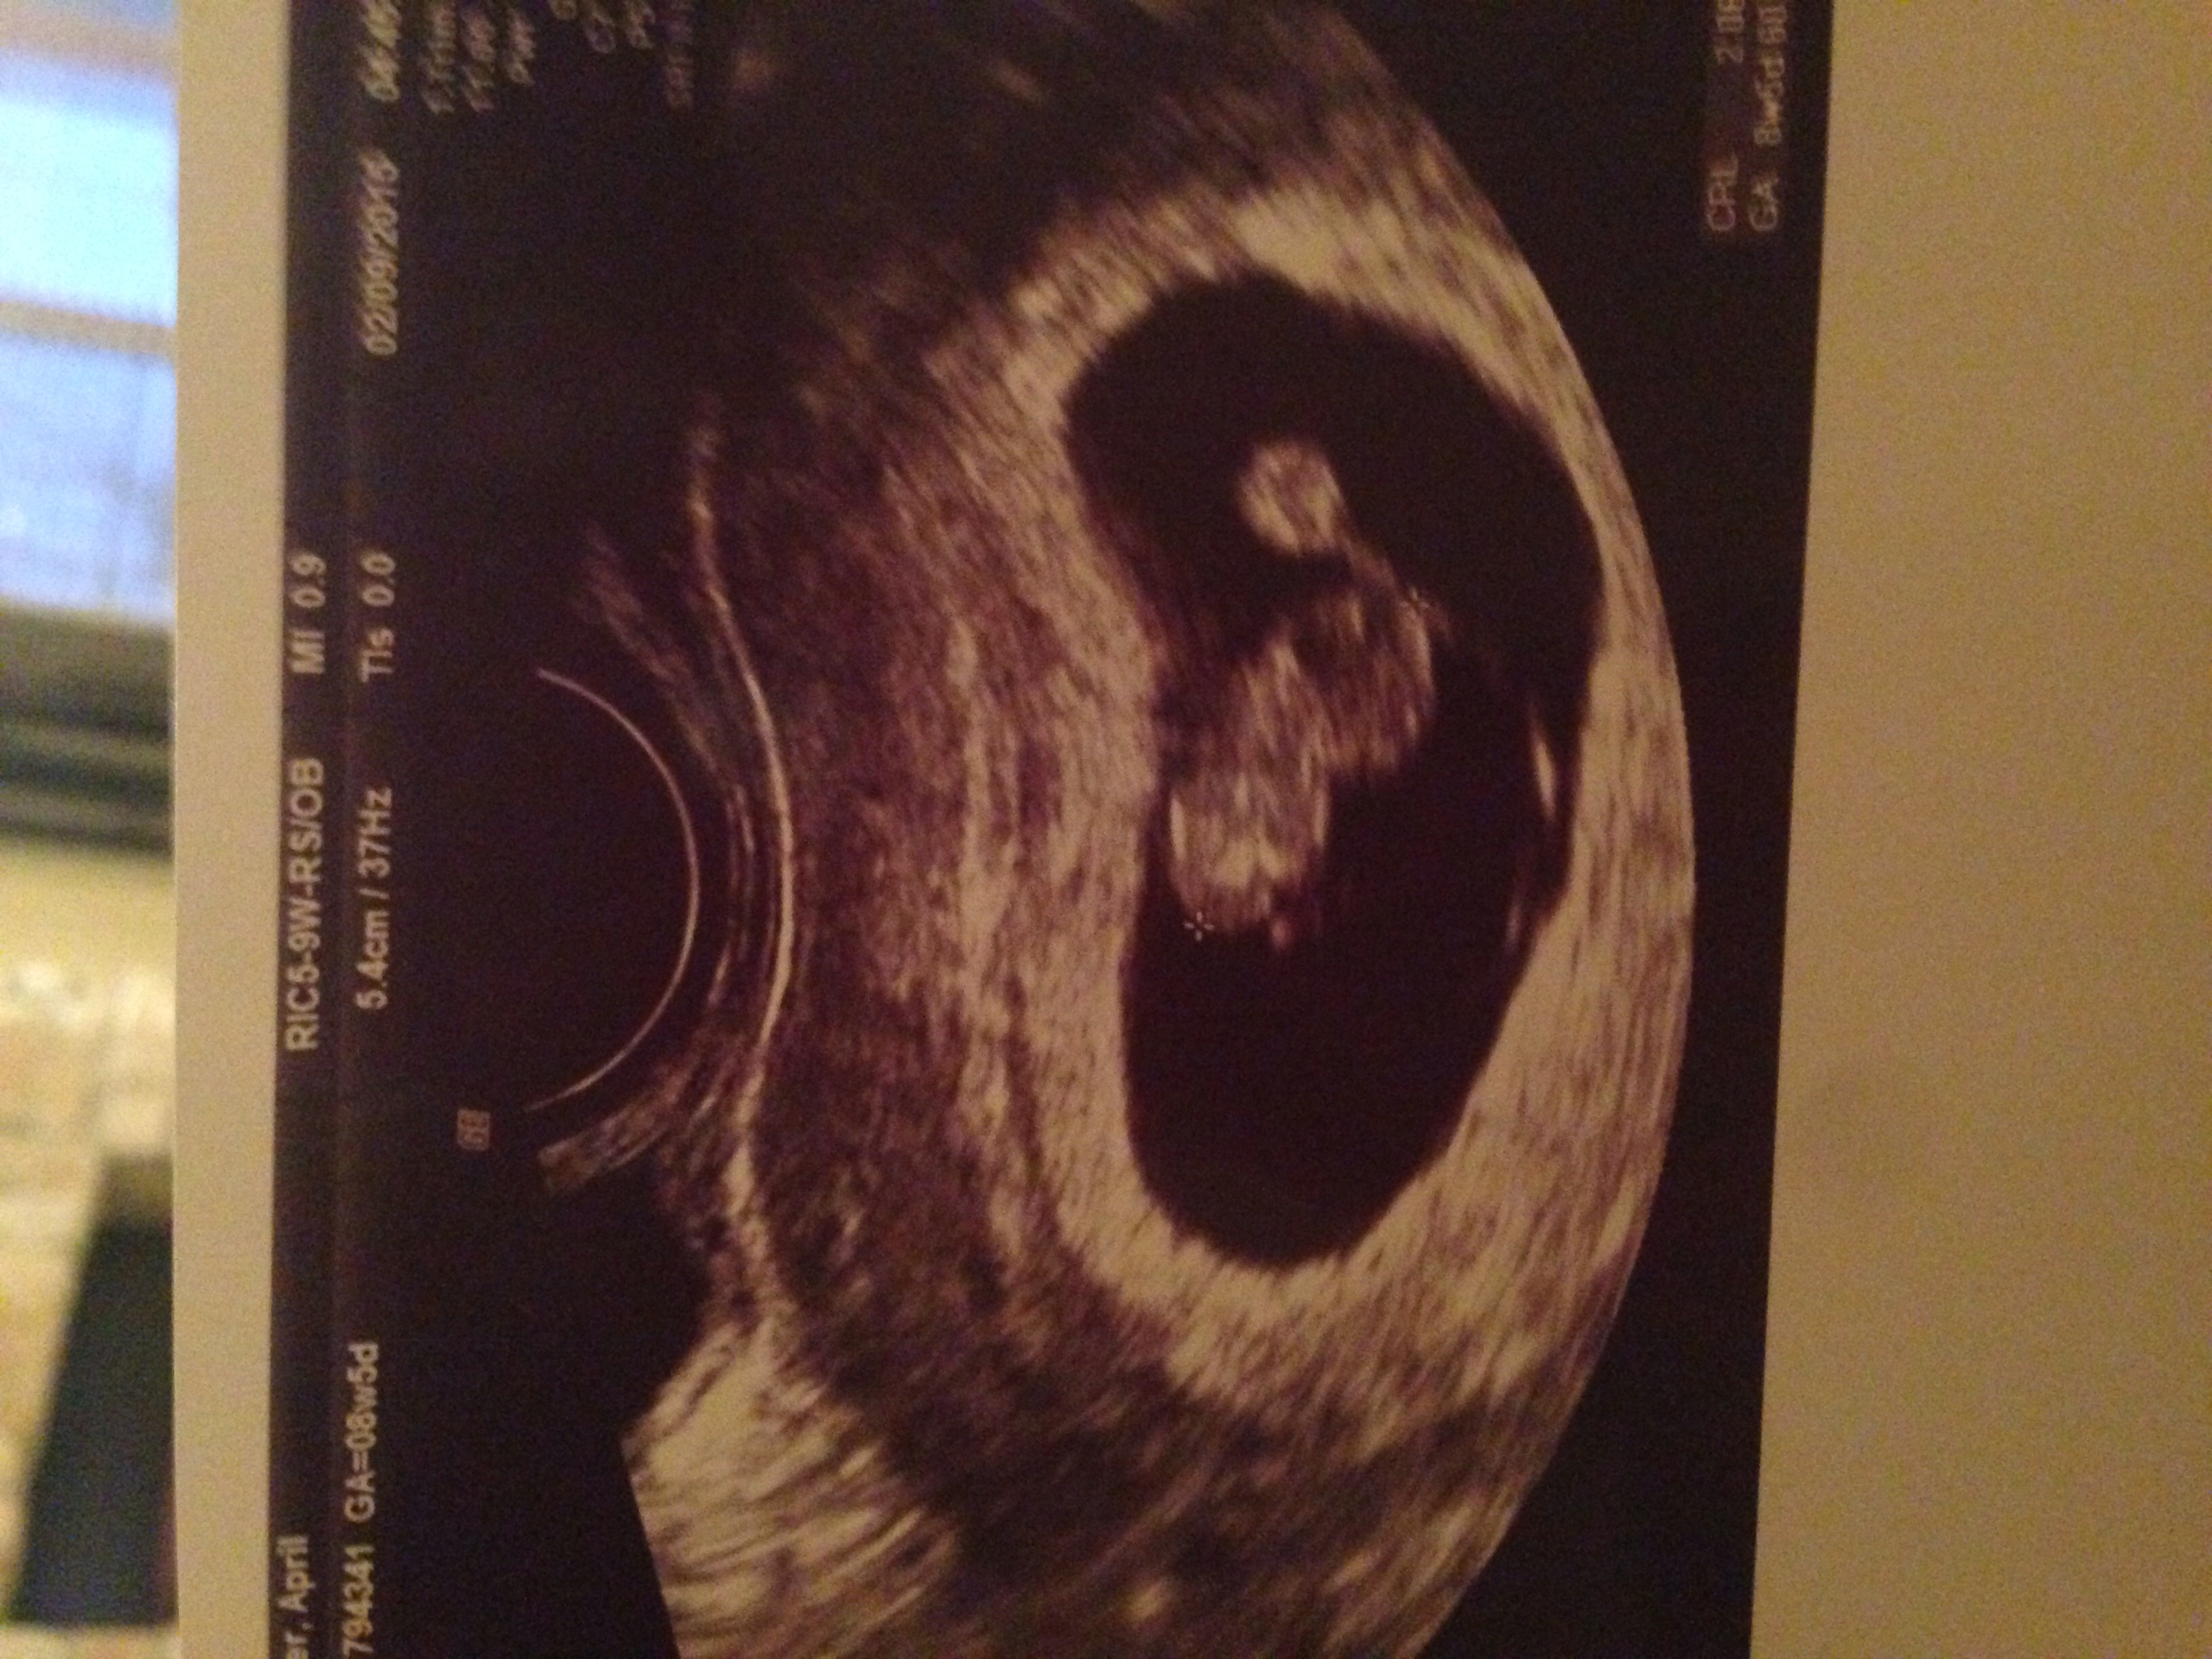

Transvaginal at 7w1d. And I know the yolk sac is on the right because my hubby asked if it was the head and they said yolk sac. ) so would that make it boy??

Second picture is 8 weeks 1 day also transvaginal